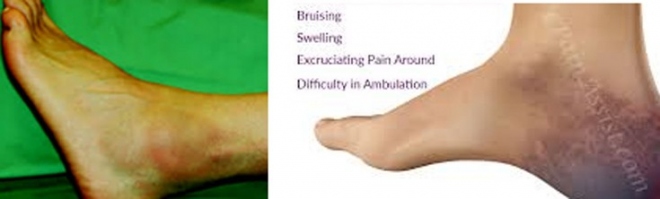

Το κάταγμα του αστραγάλου δημιουργεί πόνο και αδυναμία κινήσεων της ποδοκνημικής, δηλαδή έκταση και κάμψη. Το πόδι πρήζεται στην περιοχή του αστραγάλου αρκετά.

Στο κάταγμα της πτέρνας ενώ η ποδοκνημική εμφανίζει φυσιολογική κινητικότητα, υπάρχει τεράστιο πρήξιμο κάτω από τον αστράγαλο και πλήρης αδυναμία ν΄ ακουμπήσει το πόδι το βάρος του.